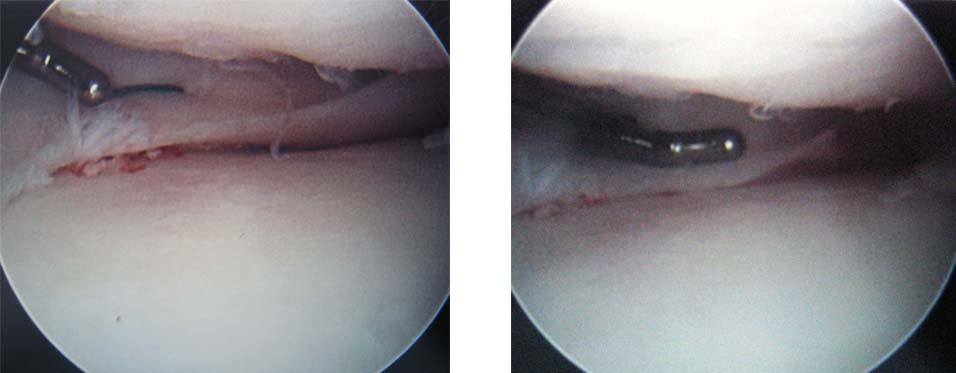

5.At this stage, the tibial graft has been fixed in place with screws (long arrows) along with its meniscus (arrowheads). On the image on the right, a 30 mm diameter femoral condyle allograft plug has been inserted into the area of maximal damage on the femur. (black arrow)

6.Once both grafts are in place, the knee wounds are closed and the meniscus (black arrows) is repaired to the capsule using standard arthroscopic techniques.